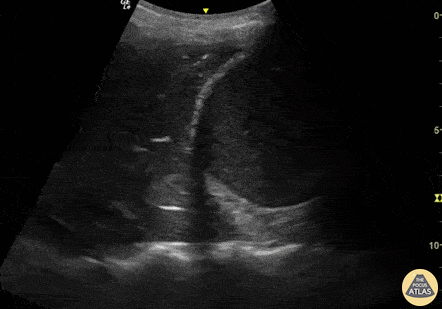

What is seen in this ultrasound?

Pleural effusion.

On ultrasound, a pleural effusion is described as an anechoic (black) or hypoechoic space above the diaphragm, often triangular in shape. Key sonographic features include the visualization of the diaphragm, adjacent organs (liver or spleen), and the "spine sign"—where vertebral bodies are seen extending above the diaphragm due to the presence of fluid.